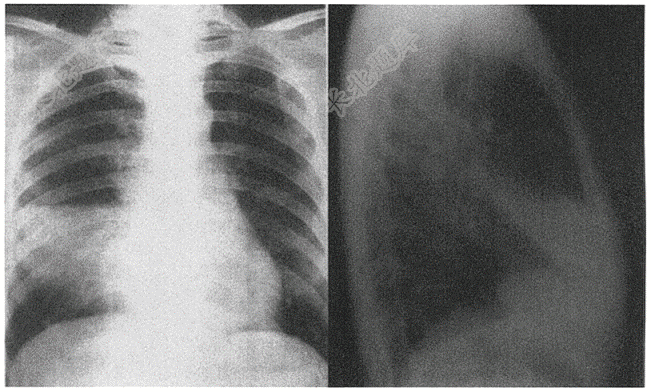

- 单项选择题男性,44岁,发热5天( )

A、右下肺炎症

B、左下肺炎症

C、右侧胸腔积液

D、右肺中叶肺结核

E、右肺中叶大叶性肺炎